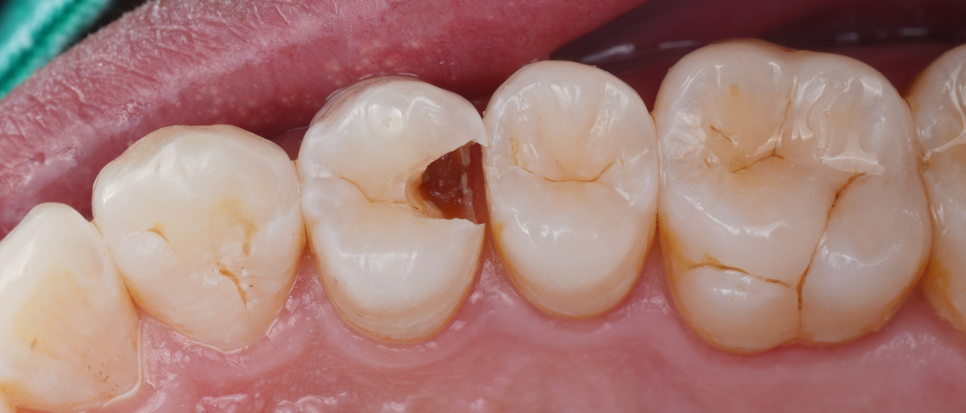

충치 부위를 깨끗하게 제거한 뒤 Se-bond를 사용해 접착층을 형성하고 여러 층으로 쌓아 올렸어요.

각 층마다 빛을 이용해 단단하게 굳힌 뒤 자연치와 같은 질감과 색을 만들어냈죠^^

레진을 올려둔 곳을 못 알아보게끔

이번 치료는 단순히 떨어진 곳을 다시 붙인 게 아니라 치아를 지켜낸 치료였어요.

촬영일 : 251020

신경치료도, 크라운도 하지 않고 치아의 형태와 기능을 그대로 유지할 수 있었죠.

그래서 이번 케이스처럼 신경치료 없이 최소삭제로 자연치 보존을 도와드리면 참으로 뿌듯하고 성취감을 느낍니다ㅎㅎ